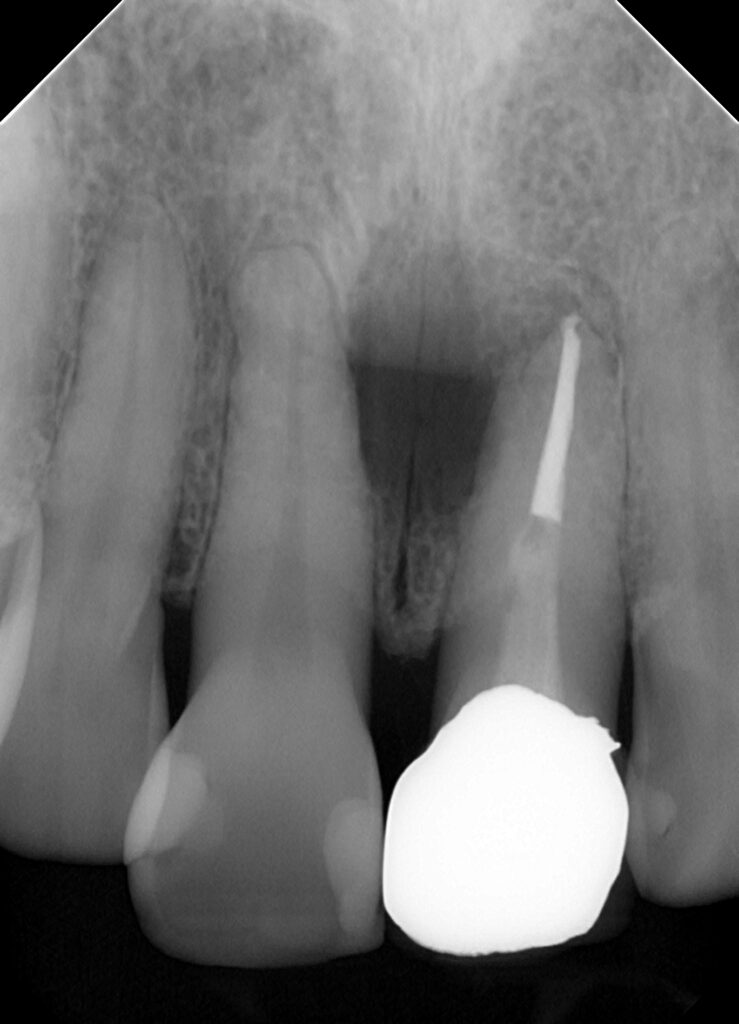

5年前に根っこの治療をしてそのあとから腫れだしてしまって放置していたらだんだん膿が出てくるようになってしまった患者さんです

前の歯医者さんで口腔外科に行って手術するしかないといわれたそうですが大学病院ではやるなら抜歯になるといわれ当法人に来院されました。

患者さんとお話して通常の根っこの治療では治らないと思うこと説明して【歯根端切除術】というやり方で処置していくことになりました。

もちろんその処置をしても完治は難しいかもしれないことも説明したうえで何年かだけでも症状出ずに使用できるからそれでいいとのことなので思い切って手術していくことにしました。

まずはその前処置として土台の除去と中にあるお薬をマイクロスープを使用して除去していく様子を動画にとりました。